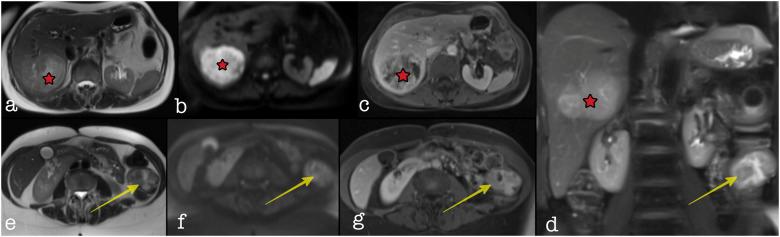

Primary leiomyosarcoma of the colon with synchronous liver metastasis.

https://cdn.ncbi.nlm.nih.gov/pmc/blobs/52e3/8961372/1a67bccf474c/10.1177_20363613221080549-fig1.jpg